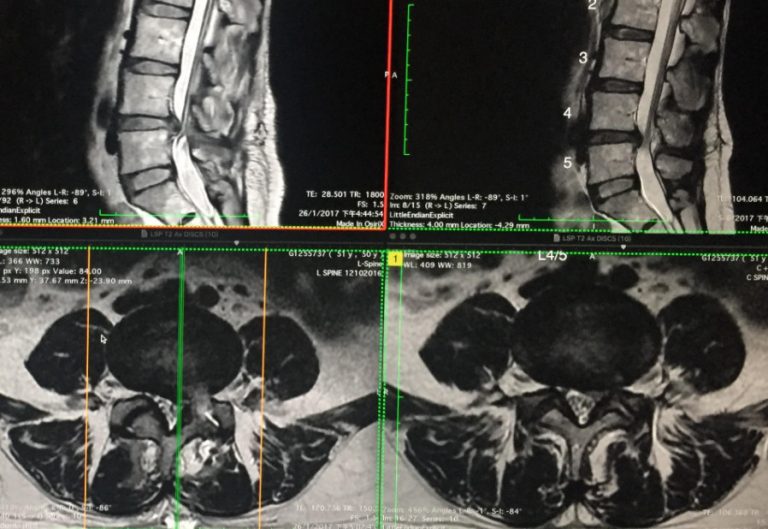

椎間盤突出微創切除手術後,醫生囑咐術後應完全避免提拿重物、不可做重力運動或過分勞動,可惜病人沒有遵行,術後三星期李女士腰椎第4、5節椎間盤再次突出(見圖三),使腿部及臀部痛楚麻痺。病人不想在短時間內再次動手術,加上情況不嚴重,便接受筆者Cox®椎間盤脊椎神經減壓治療。經過四個月達30次的Cox®椎間盤減壓治療後,病人腿部、臀部的疼痛及麻痺消失,作磁力共振對比發現術後再突出的椎間盤明顯縮小收回,之前壓到神經的情況也改善不少(見圖四)。病人現在保持每月作Cox®椎間盤減壓保健治療來維持椎間盤的狀況。

(左圖三) 術後3星期因做家務腰椎第4/5 節椎間盤再次突出 (右圖四) Cox®椎間盤脊椎神經減壓治療後, 再突出的椎間盤明顯縮小及回收, 之前壓著神經的影象也改善不少